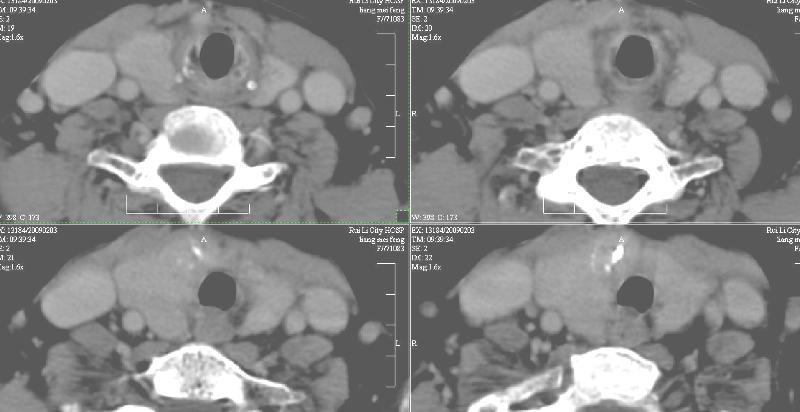

增强:1、双侧甲状腺肿。2、平扫甲状腺内多发占位病变,增强显示不清楚,境界欠清,请结合临床考虑甲状腺瘤。

右侧甲状腺占位及右侧淋巴结肿大,考虑甲状腺癌!期待结果!

强化效果一般,未见明显恶性征象。

1)弥漫性甲状腺肿。2)甲状腺多发性腺瘤?